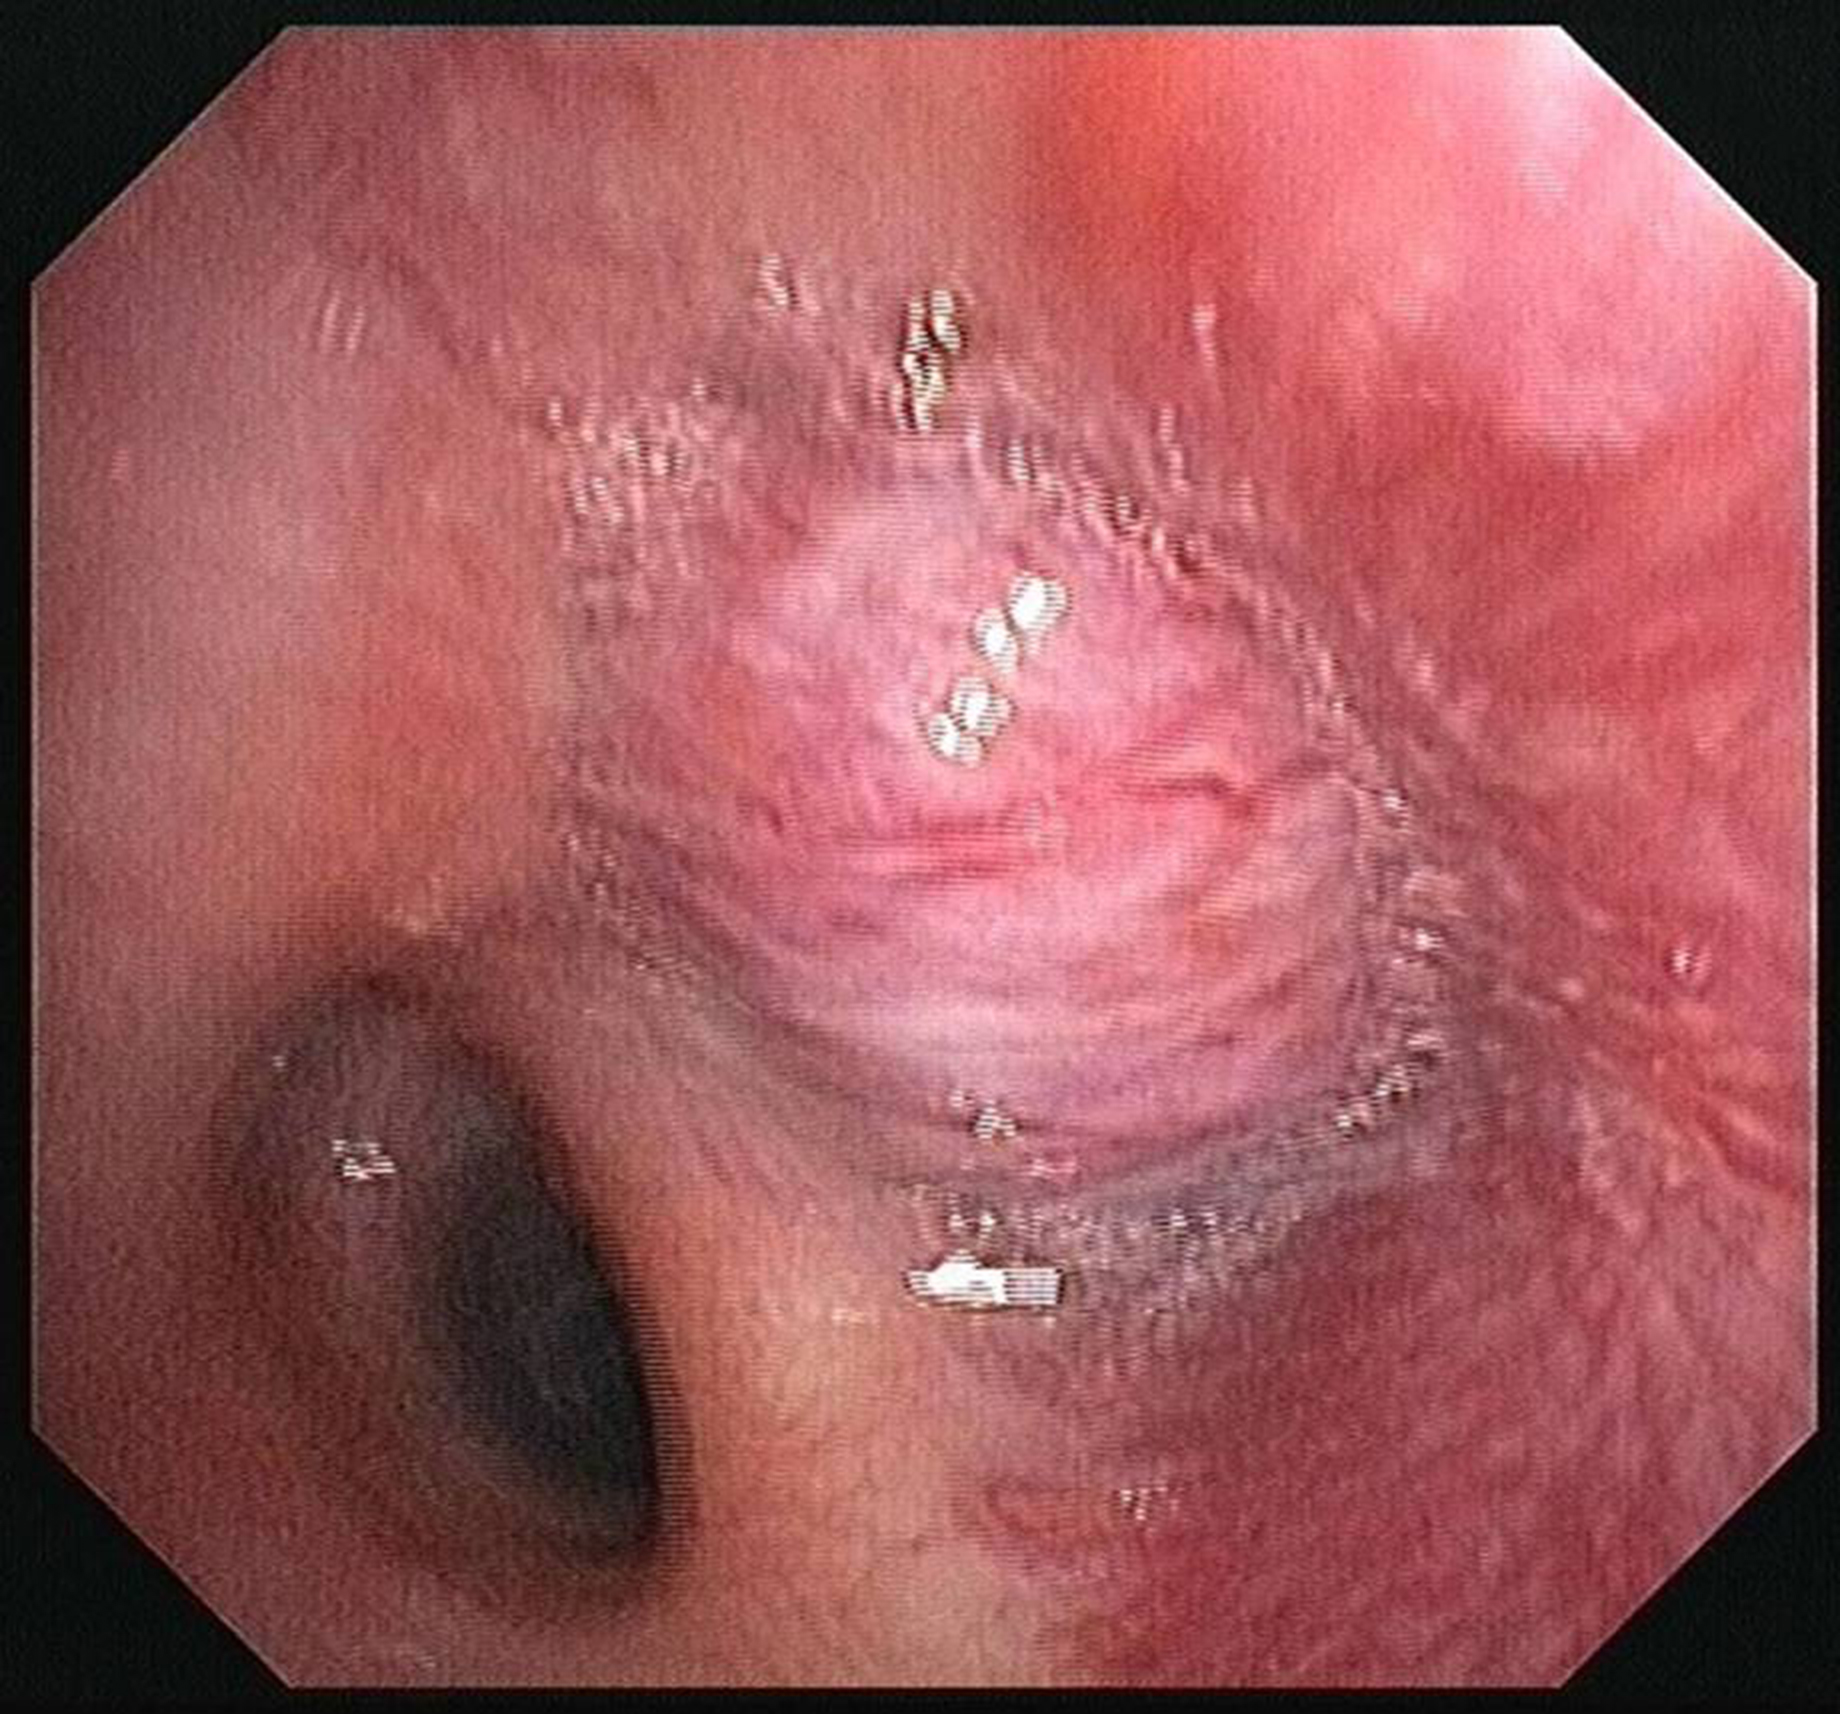

- Figura 1 (Português (Portugal))